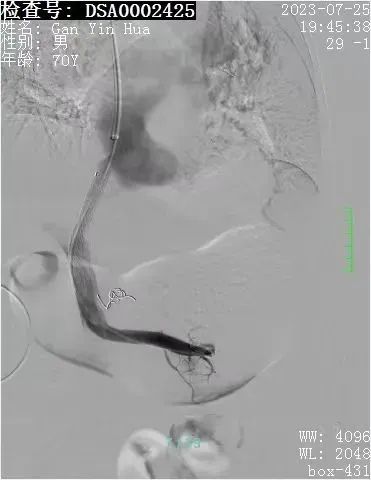

患者甘某某,男性,70岁,是一名乙型肝炎肝硬化患者,患者反复多次呕血,病情紧急,取得家属同意后,肝病科主治医师在科室人员的配合下,熟练进行门静脉穿刺、曲张食管-胃底静脉栓塞、门静脉球囊扩张以及支架植入术等一系列专业操作,约1个半小时,手术顺利完成,患者转回肝病专科进一步治疗后,好转出院。

经颈静脉肝内门体分流术(TIPS)被业内誉为“外周介入的技术高峰”,是借助介入器材,利用外科分流术的基本原理,达到治疗和预防食管-胃底静脉曲张破裂出血和顽固性胸腹水等门静脉高压并发症的一种治疗方法,对于急性消化道出血的高风险肝硬化患者来说,早期应用TIPS可以提高患者的生存率,降低再出血的发生率。